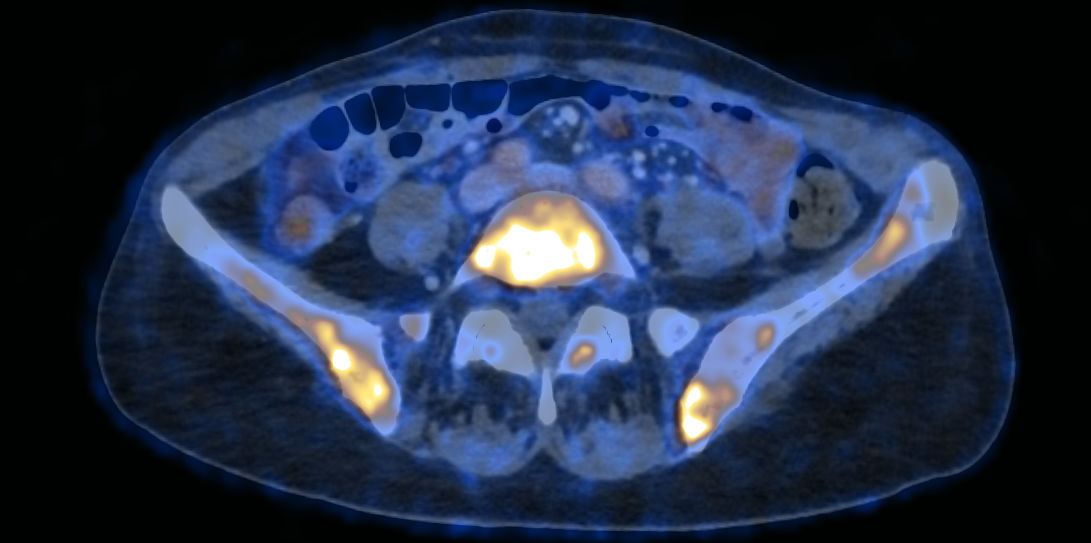

(22.08.2024, HOF, Bilder: Birgit Koell und Nuklearmedizin Innsbruck/Virgolini/Rossetti)